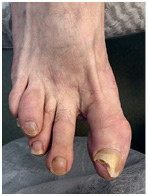

Иллюстрация к книге — Подология понятно. Важен каждый шаг. Справочник по проблемам подологии для клиентов и мастеров эстетики [i_269.jpg]

Иллюстрация к книге — Подология понятно. Важен каждый шаг. Справочник по проблемам подологии для клиентов и мастеров эстетики [i_270.jpg]

Результат работы за 5 месяцев: подолог использовал крючковые коррекционные системы, а хирург сделал пластику внутреннего бокового валика (из-за хронических воспалений боковой валик стал гипертрофированным и давил на ноготь, от чего клиент испытывал постоянный дискомфорт)